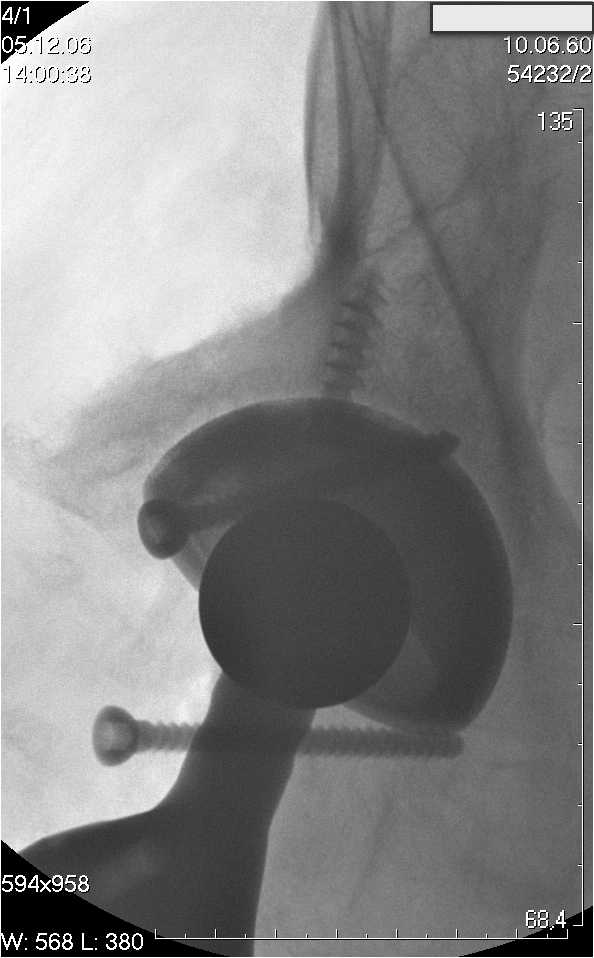

Уважаемые коллеги.В 3 Центральный Военный Клинический Госпиталь имени А. А. Вишневского, что в Красногорске, Московской области, в отделение эндопротезирования крупных суставов поступил пациент 1960 года рождения Жалобы при поступлении: на боли в области левого тазобедренного сустава (больной указывает на точку расположенная в середине условной линии между седалищным бугром и большим вертелом), усиливающиеся в начале ходьбы, при опоре на левую ногу с иррадиацией болей по наружной и наружно-задней поверхности левого бедра, левый коленный сустав; снижение объема движения в левом тазобедренном суставе, снижение опорной способности левой нижней конечности, хромоту на левую ногу, необходимость использования дополнительной опоры (костыли) при ходьбе, снижение объема двигательной активности из за болей в суставе.В анамнезе: Со слов больного, согласно медицинских документов, в 1989 году получил травму левой нижней конечности: закрытый перелом левой вертлужной впадины с центральным вывихом головки левой бедренной кости. Лечился консервативное. В процессе лечения сформировался посттравматический артроз, укорочение левой нижней конечности до 5 см. 25.04.2005 года в Подольском Окружном Госпитале Министерства Обороны выполнено: одномоменто, остеосинтез заднего края вертлужной впадины фрагментом резецированной головки бедренной кости и тотальное эндопротезирование левого тазобедренного сустава бесцементным эндопротезом "VERSIS ET" с бесцементной чашкой TRILOGY. Послеоперационный период осложнился ранним нагноением области эндопротеза, в результате санаций очага инфекции и антибиотикотерапии, активного промывного дренирования антисептиками, послеоперационная рана зажила. После операции, со слов больного, через два месяца в полном объеме стал нагружать левую нижнюю конечность. В течение полгода, после операции чувствовал себя вполне удовлетворительно. С марта 2006года стал отмечать появление болей в области тазобедренного сустава, то в области паха, то в области левой ягодицы. С августа месяца отмечает те жалобы, с которыми он сейчас к нам обратился. Температура тела, после заживления раны, нормальная. В анализах крови, лейкоциты около 7 тыс, формула нормальная, СОЭ 12 мм ч. Локально: при осмотре обеих нижних конечностей, анатомическая ось конечности не нарушена; отмечено относительное укорочение левой н\конечности на 1.5 см., гипотрофия мышц левого бедра 3 см, голени 2 см, симптом. Объем движений в тазобедренных суставах: правый~ сгибание- 60 гр, разгибание-180 гр ,отведение- 35 гр, левый~ сгибание- 110 гр , разгибание-170 гр , отведение-15 гр. Контуры других суставов н/конечностей обычные, объем движений в них не страдает. Пульсация на артериях конечностей удовлетворительная. Неврологические нарушения конечностей отсутствуют, рефлексы на обеих н/конечностях одинаковые, чувствительных нарушений нет. Осевая нагрузка на левую нижнюю конечность вызывает боль в точке расположенная в середине условной линии между седалищным бугром и большим вертелом. Отмечается пигментация и пастозность нижней трети обеих голеней и стоп, характерная для посттромботической болезни. На Цветном дуплексном сканировании сосудов нижних конечностей: Нестенозирующий атеросклероз обеих бедренных и подколенных артерий . Гемодинамически значимых препятствий кровотоку в магистральных артериях ног не выявлено. Глубокие и поверхностные вены нижних конечностей проходимы. Умеренная недостаточность клапанов подколенных вен. Данных за тромбоз глубоких вен на момент осмотра не получено.А вот что пишет наш рентгенолог: На серии рентгенограмм области левого тазобедренного сустава определяется тотальный бесцементный эндопротез. Вокруг тени чашки эндопротеза определяется ободок остеорезорбции. Кроме того, визуализируется деформированный костный винт фиксирующий консолидированный отломок вертлужной впадины, вплотную прилегающий к тени чашки эндопротеза. Заключение: Рентгеновские признаки нестабильности чашки тотального эндопротеза. Лучевая нагрузка: 6 мЗв. У нас в отделении разошлись мнения: начальник мой утверждает, после сравнения снимков, принесенных больным от августа и октября 2006года и наших рентгенснимков, что у больного нет нестабильности вертлужного компонента, и что надо назначит курс консервативной терапии: препараты кальция, миакальцик, увеличить осевую нагрузку на левую нижнюю конечность, ЛФК направления на укрепление мышц бедра, ягодиц, физиолечение. А я утверждаю, что у больного клиника нестабильности вертлужного компонента, и необходима ревизия вертлужного компонента, не исключено даже наличие инфекции под чашкой эндопротеза (не смотря на отсутствие клинических признаков инфекции). В результате проводимой консервативной терапии, боли у больного усилились. Помогите рассудить нас, мы готовы выслушать ваши мнения по этому поводу. С уважением Батал Шушания.3 ЦВКГ имени А. А. Вишневского

Ув. Коллега.Четких рентгенологических признаков нестабильности вертлужного компонента действительно нет. Здесь, кроме нестабильности, можно искать причину в поясничный отдел позвоночника(Hip-spain синдром - всё-таки 15 лет ходил с укорочением),либо сделать спиральный КТ и посмотреть, нет ли несращения в области старого перлома вертлужной впадины. Зачастую ложные суставы подвздошной, седалищной, а иногда и лонной костей являются причинами несостоятельности эндопротезов.

Уважаемый д-р Батал,

Ситуация не столь однозначная как Вам это видится. По подробно описываемой клинике с большей вероятностью речь идет о проблемах

поясничного отдела позвоночника. Есть зона остеолиза вокруг чашки, но как правило, дополнительный винт держит чашку достаточно хорошо, и даже при наличии микроподвижности, это не сопровождается столь ярким болевым синдромом. Поэтому, я бы сделал следующее: МРТ позвоночника, пункцию ТБС для исключения инфекционного процесса. Ревизию рассматривал бы как крайний вариант, учитывая выполненную костную пластику и отсутствие явных признаков нестабильности.

уважаемый коллега, Антон Вакуленко. Спасибо за четкий, расписанный по пунктам план действий. При поступлении пациента в отделение, я думал точно как вы. Но на следующий день, выполнил многопроеционное рентгенисследование, показал невропатологу, и доложил начальнику отделения о больном.После разбора пришли к следующему, да у больного действительно нестабильность вертлужного компонента, есть зона лизиса в месте костного аутотрансплантата, а в месте фиксаци чашки деротационным винтом четко выраженный контакт чашки с костной тканю. Мы пришли к выводу,что лизис костного аутотрансплантата из за осевой перегрузки на фоне незавершенного ремоделирования (вес больного 130 кг). Потому мы и приняли план вышеуказанного лечения. Провели беседу с больным, больной согласился с нами. Через 3-6 месяцев мы оценим эффективность лечения и доложу. Возможно и придется тогда идти на ревизию с заменой только вертлужного компонента а может и придется удалить весь эндопротез с установкой спейсера.. посмотрим.....

> компонента, есть зона лизиса в месте костного аутотрансплантата,

> а в месте фиксаци чашки деротационным винтом четко выраженный

> контакт чашки с костной тканю. Мы пришли к выводу,что лизис